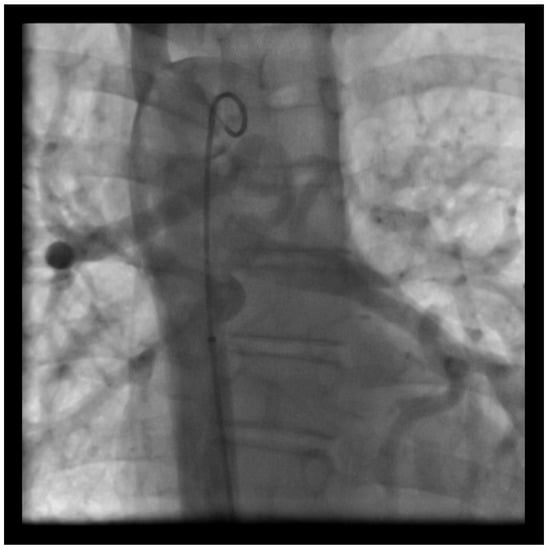

- Latus, H.; Apitz, C.; Moysich, A.; Kerst, G.; Jux, C.; Bauer, J.; Schranz, D. Creation of a functional Potts shunt by stenting the persistent arterial duct in newborns and infants with suprasystemic pulmonary hypertension of various etiologies. J. Heart Lung Transplant. 2014, 33, 542–546. [Google Scholar] [CrossRef] [PubMed]